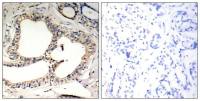

WB, IHC-P

Various whole cell extracts (30 μg) were separated by 7.5% SDS-PAGE, and the membranes were blotted with HGF (alpha subunit) antibody (GTX129003) diluted at 1:500 and competitor's antibody (sc-7949) diluted at 1:100. The HRP-conjugated anti-rabbit IgG antibody (GTX213110-01) was used to detect the primary antibody, and the signal was developed with Trident ECL plus-Enhanced.